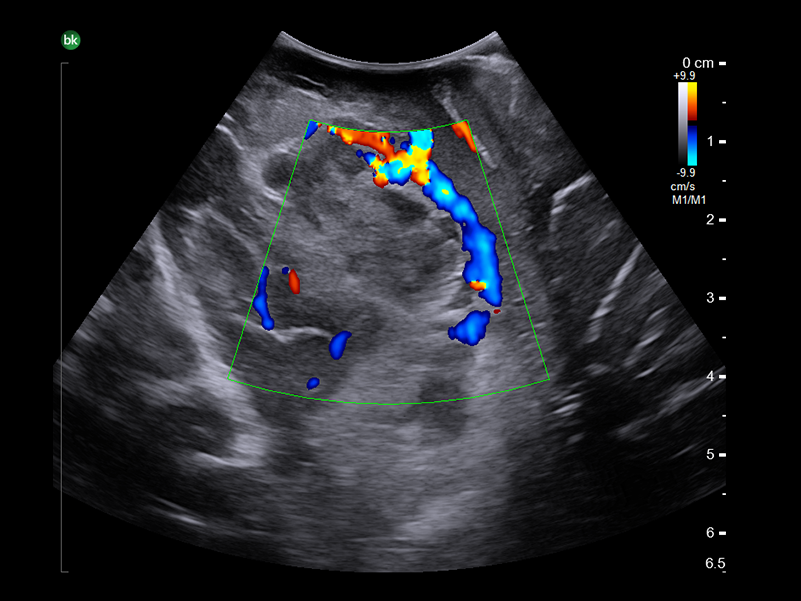

REAL-TIME VISUALIZATION HAS NEVER LOOKED THIS GOOD

- Enhanced Visualization: Improved algorithms for greater details around lesion borders, and automated high-resolution image settings.

- Monitor Progress: Compare live images with previous scans simultaneously using Dual Live Compare, Picture in Picture, or Stored Image Compare.